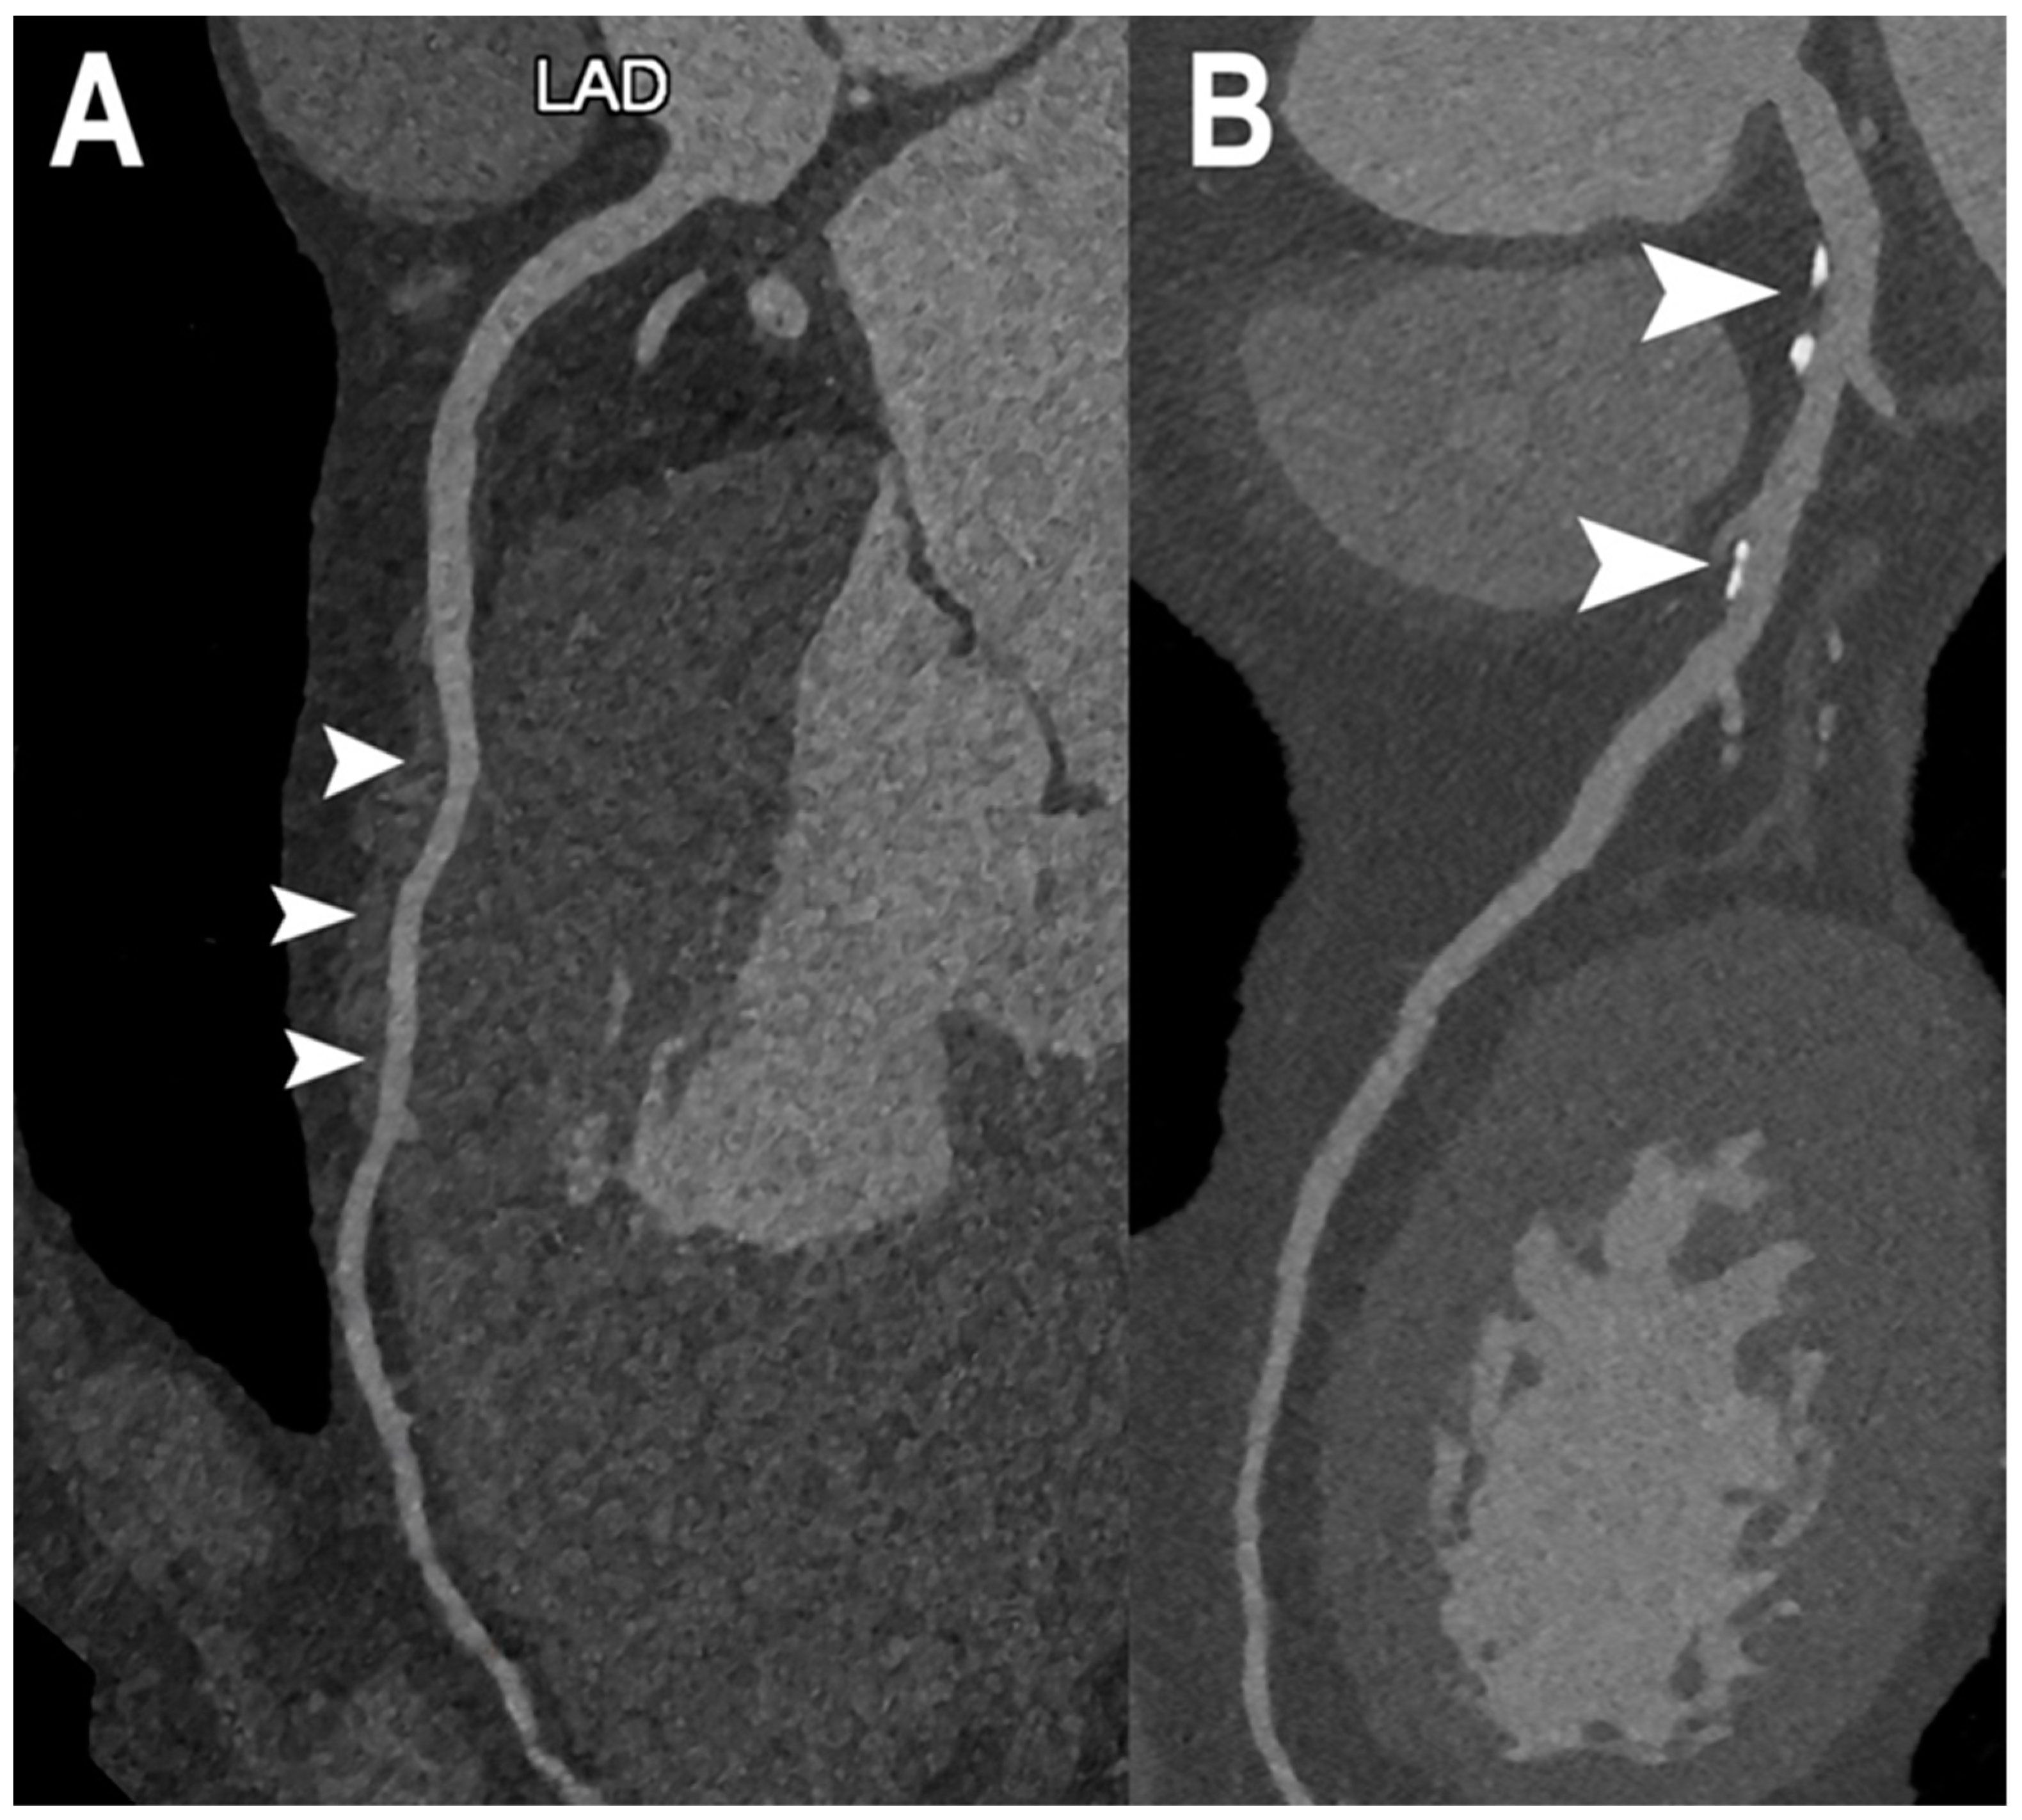

| Si-Mohamed et al. [30] | 2022 | In vivo (human) | 14 | Coronary lumen | Proportions of score improvement with PCCT images (compared to EID-CT images) for overall quality and diagnostic confidence were 57% (95% CI: 41, 72) and 55% (95% CI: 39, 70), respectively, and 48% (95% CI: 33, 63), 51% (95% CI: 35, 67), and 69 (95% CI: 53, 82) for coronary proximal lumen, coronary distal lumen, and coronary wall, respectively. |

| Rotzinger et al. [31] | 2021 | In vitro | Coronary lumen | PCCT provided higher spatial resolution, lower noise magnitude, and superior lipid core detectability than EID-CT. | |

| Koons et al. [12] | 2022 | In vitro | Coronary lumen | PCCT demonstrated an improvement in plaque/lumen delineation and a more accurate stenosis quantification for all plaques than EID-CT. | |

| Allmendiger et al. [32] | 2022 | In vitro | Coronary lumen | An image reconstruction algorithm using PCCT decreases blooming artifacts caused by heavily calcified plaques and improves image interpretability. | |